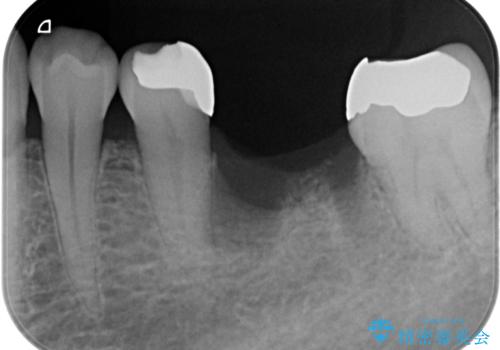

- 他院で行われた抜歯後の機能回復について相談に来院されました。

インプラント治療、入れ歯と比較し、前後の銀歯や詰め物の問題も一緒に治療のできるブリッジ治療を選択されました。

ブリッジは早期に審美性・機能性を回復できる治療法です。